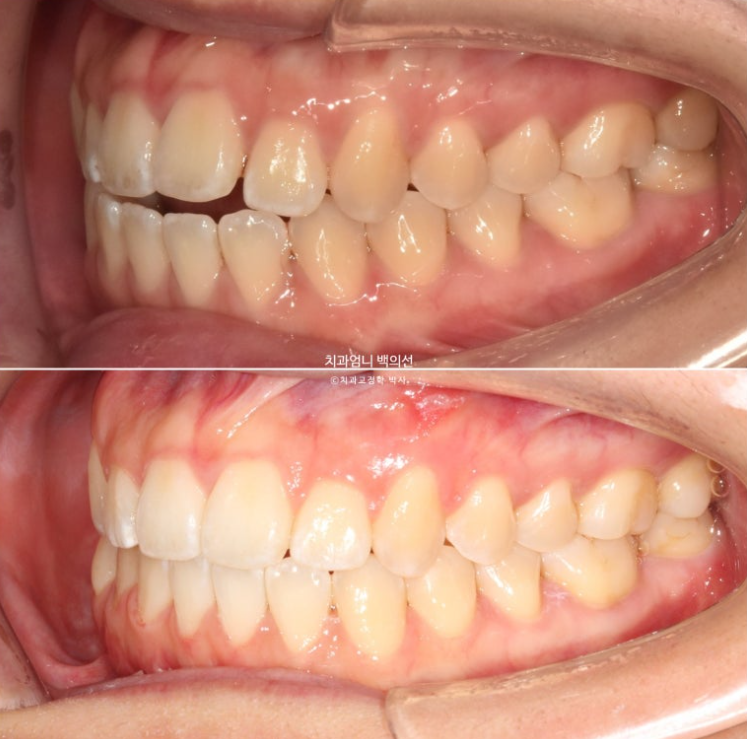

24년 12월에 재교정을 위해 내원하신 분 입니다.

중학교때 교정을 했으나 철사유지장치가 떨어지면서 앞니가 다시 틀어진 상태입니다.

앞니 높낮이 단차와 개방교합도 보입니다.

파란 화살표 송곳니는 안쪽으로 쓰러져 있습니다.

이제 전후 비교 보겠습니다.

24.12~25.06

개방교합 뿐 아니라 철사의 변형으로 쓰러져 있던 송곳니도 세웠습니다.

원래 좋았던 교합은 잘 유지가 되었습니다.

6개월간 앞니 부분교정의 변화 치고 드라마틱 합니다.